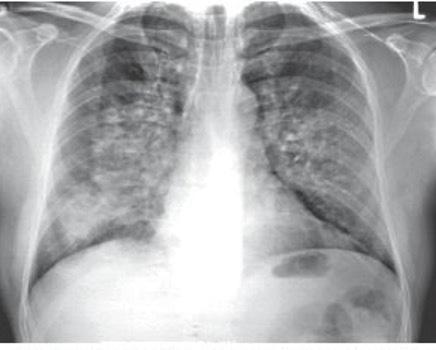

Radiología:

Cardiomegalia

Signos de congestión pulmonar.

Radiografía: cardiomegalia con hipertensión venosa pulmonar